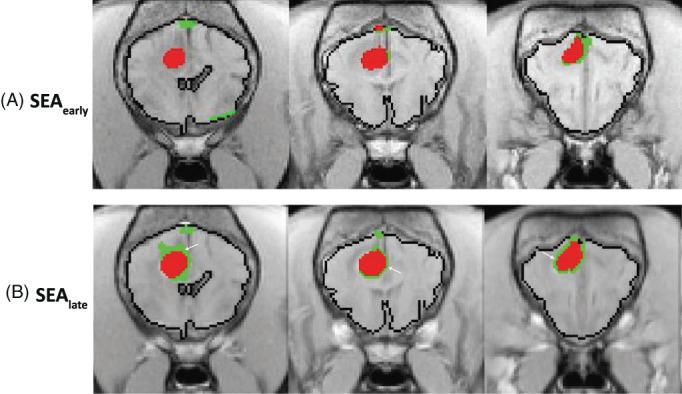

In a 2-arm study, images from a prospective dynamic contrast-enhanced (DCE; n = 15) and a retrospective archived magnetic resonance imaging study (n = 63) were analyzed by DCE and subtraction enhancement analysis (SEA) to quantify BBB permeability in affected dogs relative to control dogs (n = 6 in each arm). For the SEA method, 2 ranges of postcontrast intensity differences, that is, high (HR) and low (LR), were evaluated as possible representations of 2 classes of BBB leakage. BBB score was calculated for each dog and was associated with clinical characteristics and tumor location and class. Permeability maps were generated, using the slope values (DCE) or intensity difference (SEA) of each voxel, and analyzed.

在一项 2 臂研究中,对前瞻性动态对比增强(DCE;n=15)和回顾性存档磁共振成像研究(n=63)的图像进行了分析,通过 DCE 和减去增强分析(SEA)来定量受影响犬相对于对照犬(每臂 6 只)的 BBB 通透性。对于 SEA 方法,评估了 2 个范围的对比后强度差异,即高(HR)和低(LR),作为 2 种 BBB 渗漏的可能代表。为每只狗计算了 BBB 评分,并与临床特征、肿瘤位置和类型相关联。使用每个体素的斜率值(DCE)或强度差异(SEA)生成了渗透率图,并进行了分析。